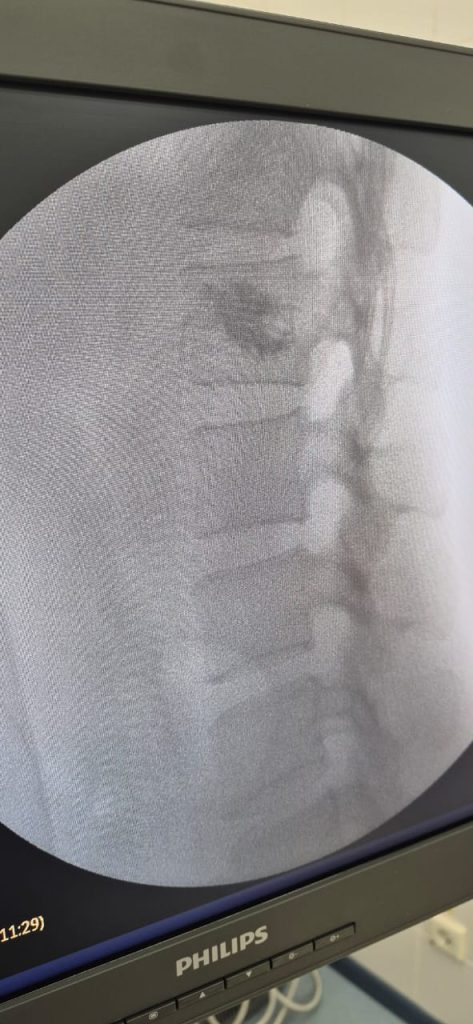

К счастью, сегодня есть современный и безопасный метод лечения — перкутанная вертебропластика. Это малоинвазивная процедура через маленький прокол, при которой в ослабленный позвонок вводится специальный медицинский цемент. Он укрепляет повреждённый участок, останавливает рост гемангиомы и быстро снимает боль. Операция длится около 20–30 минут, проводится без общего наркоза, а вставать можно уже через пару часов.

В Городской многопрофильной больнице Тараза такие операции выполняются ежедневно опытными нейрохирургами на современном оборудовании. Важно, что вертебропластика доступна по ОСМС, то есть бесплатно для пациента при наличии медицинских показаний. Если на МРТ вам выявили гемангиому или появились боли в спине, лучше не откладывать визит к специалисту. Своевременное обследование и лечение позволяют избежать опасных осложнений и сохранить качество жизни.